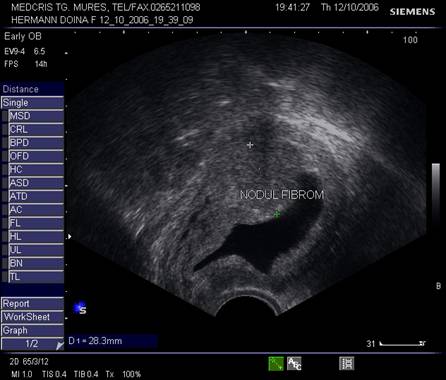

9.Sarcina si fibromul uterin

Cea mai comuna tumora uterina - leiomiomul - poate fi detectata si masurata inca de la inceputul sarcinii. Fibromul poate complica sarcina in functie de marime si pozitie. Nodulul subseros pediculat foarte rar se poate complica, in schimb nodulul submucos sau intramural creste riscul de avort spontan sau nastere prematura, dar peste 75% din aceste paciente duc sarcina la termen. Cea mai frecventa complicatie a fibromului in sarcina este necroza aseptica (25%) de obicei moderata, ea poate aparea si in lauzie. Cresterea fibromului in sarcina a fost notata in circa 22% dintre fibroame.[12]

Fibromul apare de obicei hipoecogen in uterul gravid, trebuind masurat si observat pe parcursul sarcinii.

Fig nr. 91. Nodul fibromatos submucos si sarcina

Fig. nr. 92. Nodul fibromatos intramural hipoecogen,

alaturi de sarcina de 12 saptamani